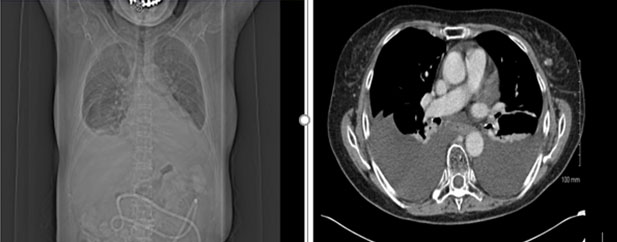

The patient was managed initially conservatively with medium-chain triglyceride low-fat diet and total parenteral nutrition. She was also commenced on octreotide, initially at 50 mcg three times a day (TDS) subcutaneously and then increased to 100 mcg TDS. She also had 4 liters of pleural fluid drained from her right lung. A chest radiograph after completion of 14 days of octreotide injections showed an increasing right-sided pleural effusion. Computed tomography of the thorax also confirmed progression of a pleural effusion, as well as her cancer (Figure 3).

Figure 3: Computed tomography scan confirming presence of bilateral pleural effusion.